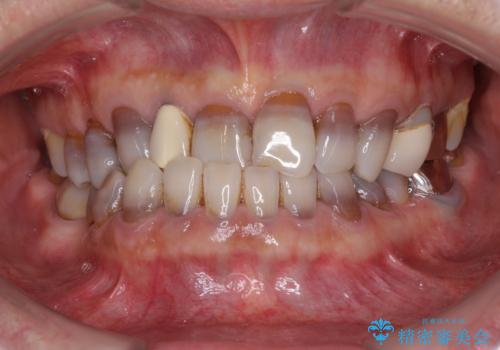

下の歯が前に出てしまう咬み合わせを治したい インビザラインによる矯正治療

- 前歯のクロスバイトを気にして来院された患者様です。

骨格的に下顎が前方位ではありますが、歯並びが改善されれば正常咬合となることが分かったため、インビザラインを用いて咬み合わせを改善していくこととしました。